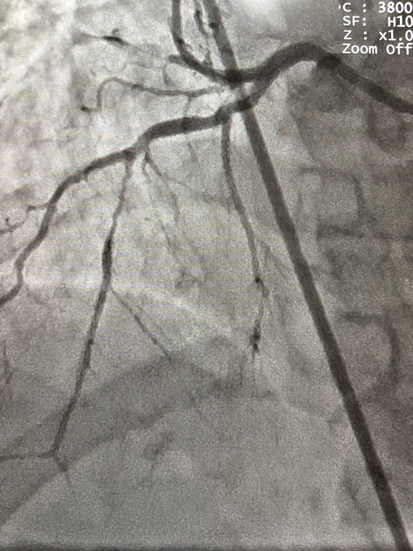

💬 Nas imagens abaixo compartilho caso de angioplastia coronária com implante de stent em paciente com dextrocardia, e cada etapa exige adaptação do olhar, da técnica e até do raciocínio anatômico. Um verdadeiro teste de precisão e concentração.